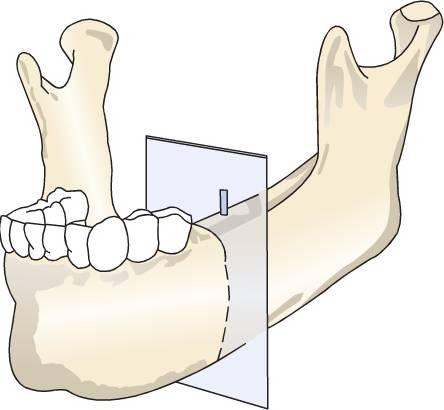

Radiografía oclusal

Las radiografías oclusales son proyecciones planas obtenidas al colocar la película dentro de la boca, paralela al plano oclusal con el haz central de rayos X perpendicular a la película para la imagen mandibular y oblicuo (normalmente a 45 grados) a la película para la imagen maxilar. La radiografía oclusal produce imágenes planas de alta resolución del cuerpo de la mandíbula o del maxilar. Las radiografías maxilares oclusales son inherentemente oblicuas y por tanto distorsionadas de manera que no son de uso cuantitativo para la odontología implantológica para determinar la geometría o el grado de mineralización del lecho implantológico. Adicionalmente, se muestran estructuras críticas como los senos maxilares, la cavidad nasal, el canal nasal palatino, pero la relación espacial con el lecho del implante suele perderse con esta proyección (cuadro 3-4).

Al ser la radiografía oclusal mandibular una proyección ortogonal, es una proyección menos distorsionada que la radiografía oclusal maxilar. En cualquier caso, los alveolos mandibulares se ensanchan en general anteriormente, y muestran una inclinación lingual en sectores posteriores, produciendo una imagenoblicua y distorsionada de los alveolos mandibulares, lo que es de muy poca utilidad en odontología implantológica. Adicionalmente la radiografía oclusal mandibular muestra la mayor anchura del hueso (es decir, la sínfisis) comparado con la anchura crestal, que es donde más se necesita información diagnóstica (fig. 3-4).

El grado de mineralización del hueso trabecular no se determina con esta proyección, y las relaciones espaciales entre las estructuras críticas, como el canal mandibular y el foramen mentoniano, y el sitio implantológico propuesto se pierden con esta proyección. Como resultado, las radiografías oclusales raramente están indicadas para las fases diagnósticas prequirúrgicas en la odontología implantológica.